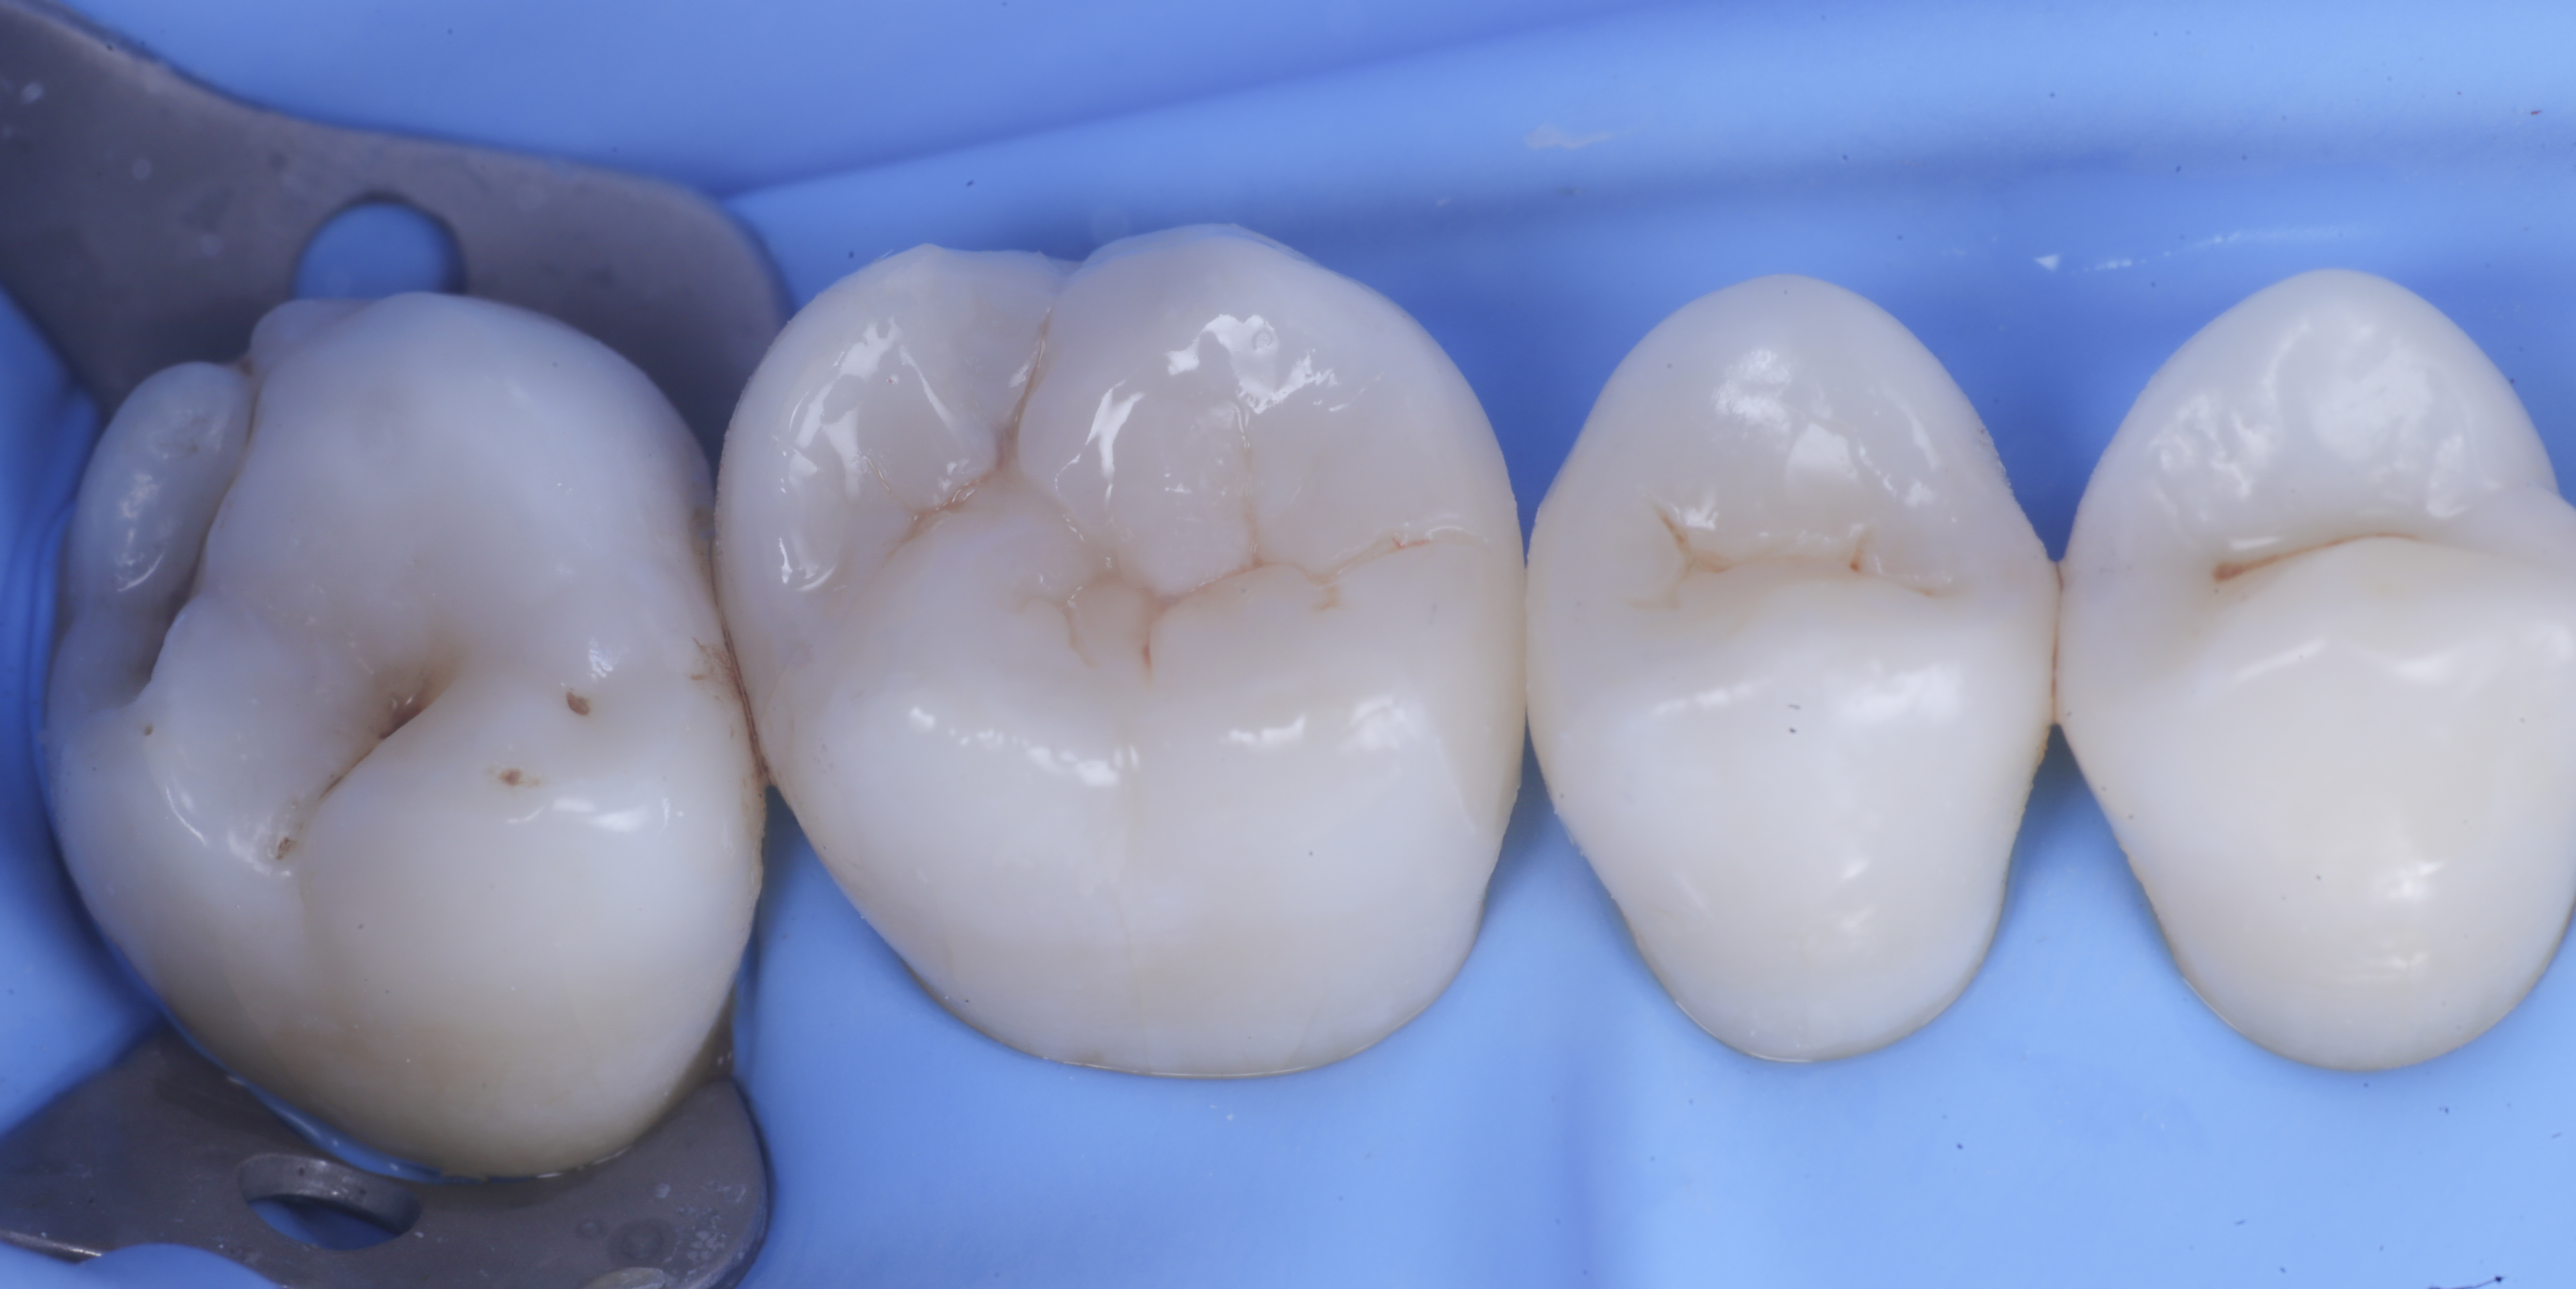

foto 11 Restauri ultimati sotto controllo occlusale